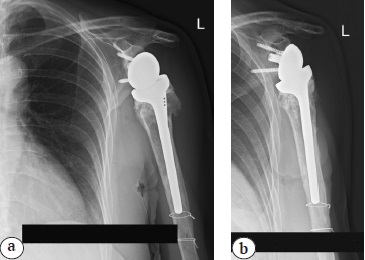

A decision was made to install a cemented endoprosthesis stem (size 1, diameter 10) because of the reduced bone quality, thin cortical walls, the risk of low integration, and the risk of endoprosthesis stem instability. The height of the shoulder component was determined by the most intact medial bone edge of the humerus. The 38/+3 cup was installed after fitting. The final radiographs are presented in Figure 5.

Fig. 5. Shoulder X-rays in the early postoperative period after left shoulder arthroplasty: a — Y-shaped view; b — direct view